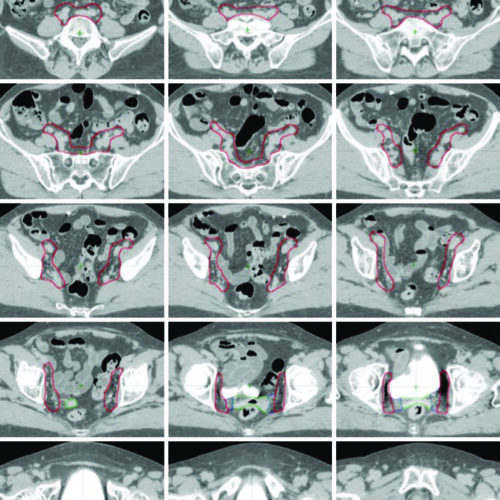

Delineamento de Volumes

Guias práticos de delineamento de volumes-alvo e órgãos de risco por sítio anatômico na radioterapia.